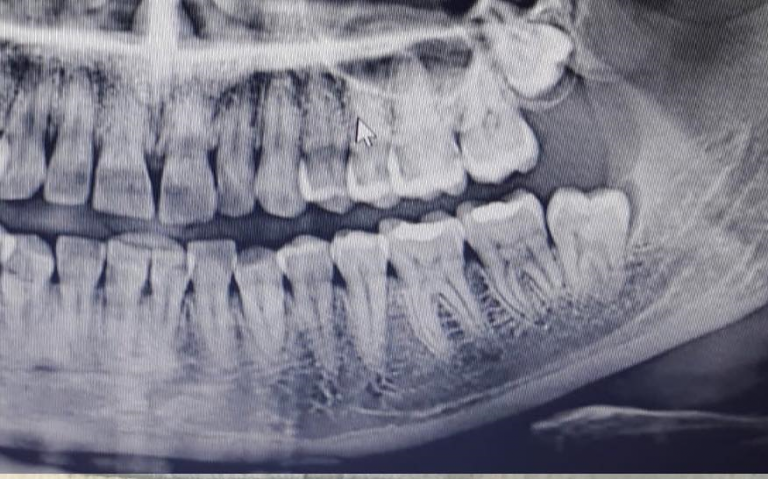

Yirmi yaş dişi veya üçüncü azı dişi, insan dentisyonunun her bir çeyreğinde bulunan üç azı dişinden birisidir. Üçü içerisinde en arkada bulunan diştir. Yirmi yaş dişi genellikle 17-25 yaşlarında sürer. Çoğu yetişkinde her bir çeyrekte bir adet bulunan dört yirmi yaş dişi vardır. Dörtten daha az ya da fazla olabilir, örneğin fazladan dişlere süpernümerer dişler denir. Yirmi yaş dişi gömülü kaldığında gelişme sürecinde olan diğer dişleri de etkiler.

Böylece bu olduğunda ya da olmadan çekilirler. Yirmi yaş dişi uzun zaman önce sorun çıkardığı tanımlanmış ve insan ağzındaki en yaygın gömülü diş olarak sorun çıkarmaya devam etmektedir. Gömülü yirmi yaş dişleri, yön, gömüklüğün derinliği, diş sürmesi için mevcut alan miktarı ve üzerlerini örten yumuşak doku veya kemik miktarına göre sınıflandırılırlar. Bu sınıflandırma yapısı doktorlara gömüklüğün olasılıklarını hesaplamalarını sağlar, dişin çekilmesi halinde görülebilecek enfeksiyonlar, komplikasyonlar.

Yirmi yaş dişleri aynı zamanda semptomların ve rahatsızlıkların varlığına göre sınıflandırılır. Gömülü yirmi yaş dişinin tedavisi herhangi bir gömülü dişin tedavisi ile aynıdır. Diş gömülü ise tedavi gömüklüğün üzerindeki enfekte doku, diş çekimi ya da koronektomi ile sınırlandırılabilir.